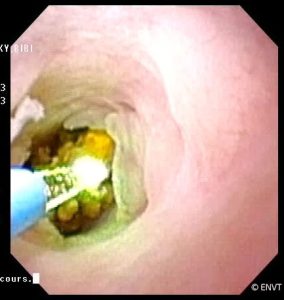

Retrait d’un calcul

Laser sur calcul

- la lithotripsie (fragmentation au laser des calculs urétraux et vésicaux),